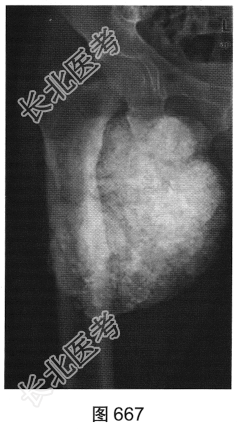

患者男性,33岁。肾衰,透析3年。右髋关节正位X线平片及左肩关节CT见图667、图668。

- 多项选择题2.[提示]患者实验室检查:肌酐334μmol/L(正常值40~135μmol/L), 血磷1.79mmol/L(正常值0.8~1.5),血钙2.34mmol/L(正常值2.1~2.7), 甲状旁腺素4617pg/ml(正常值15~85)。结合上述X线和CT表现,患者应诊断为( )